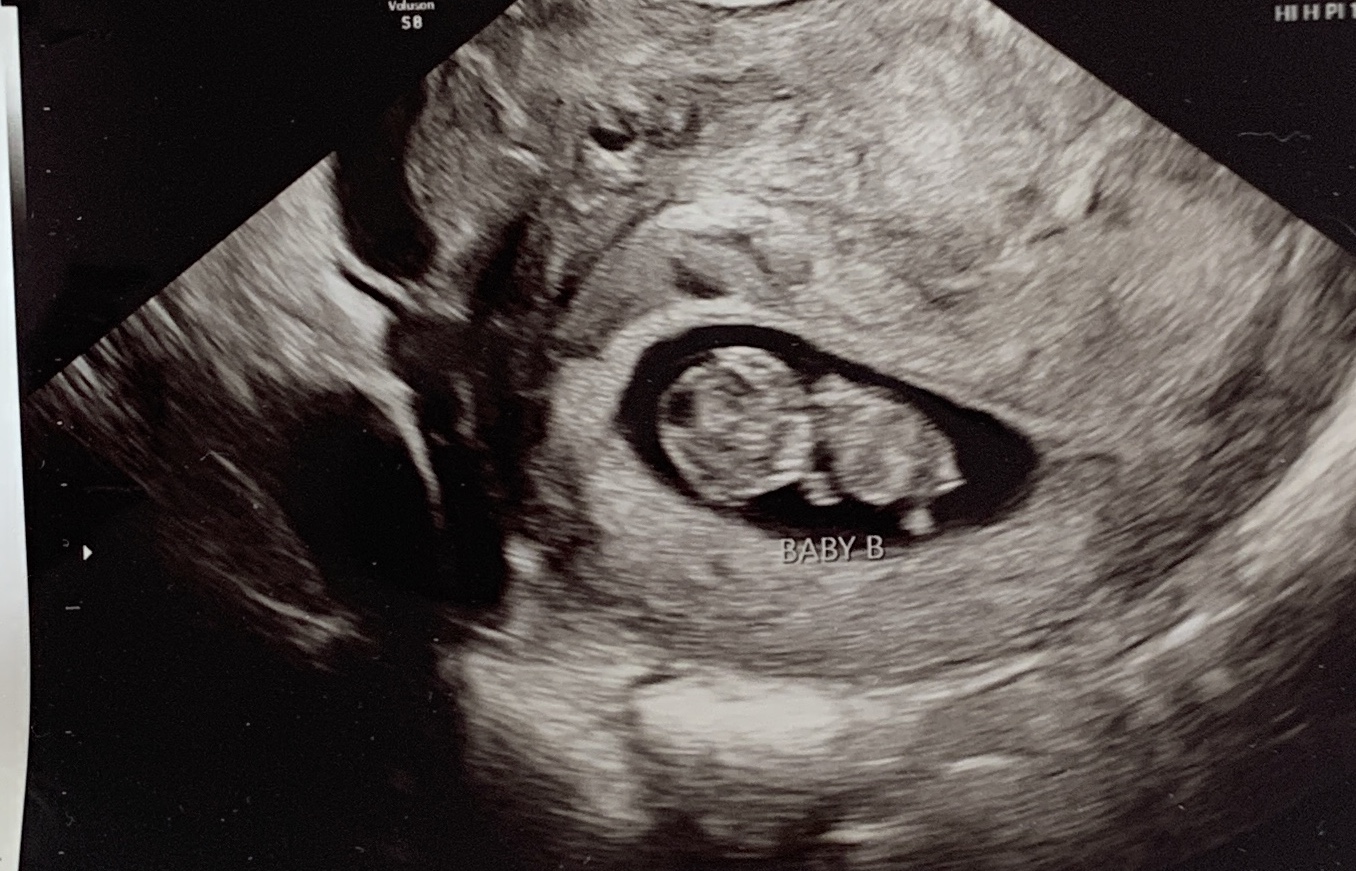

Back with some new ultrasound pics! 12w3d here :)

Attachment 42688

While earlier than I like to guess I'll give a guess of Twin A being a boy and Twin B being a girl.

Thanks for the guess! My gut says one boy and one girl too, but we'll see! :)

Well, blood test confirms one boy and one girl! We'll have to wait until the next scan to confirm which twin is which, but looks like you were right. :)

You were right! Twin A is the boy; twin B is the girl. :)